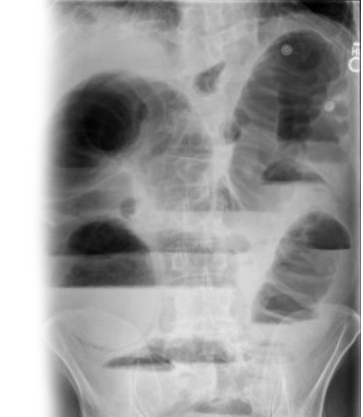

Обзорная рентгенография органов брюшной полости – важный метод исследования, который применяется для исключения проявлений острой хирургической патологии: кишечной непроходимости и свободного газа в брюшной полости. Эта неинвазивная диагностика позволяет получить информацию о состоянии органов брюшной полости, таких как желудок, кишечник, печень, желчный пузырь и поджелудочная железа.

Показания для обзорного рентгена брюшной полости:

• боли в животе;

• рвота;

• вздутие кишечника;

• кишечная непроходимость;

• перфорация полого органа;

• запоры или понос;

• подозрение на наличие опухолей в органах брюшной полости;

• гиперпневматизация кишечника.